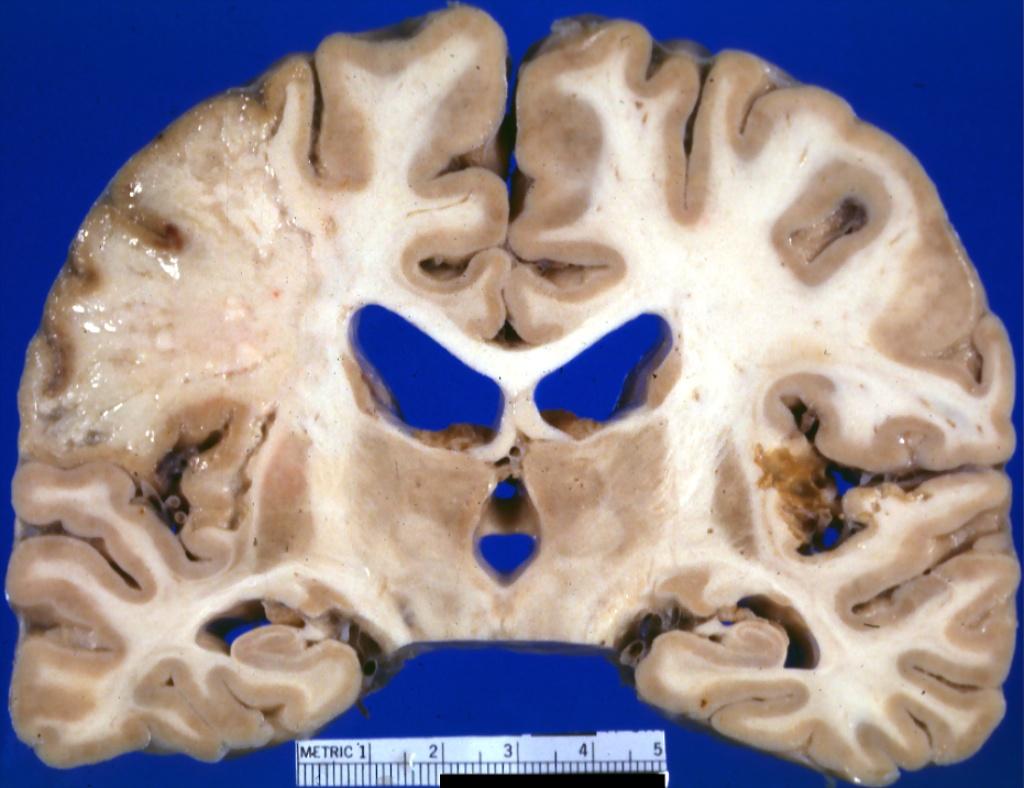

Pathology